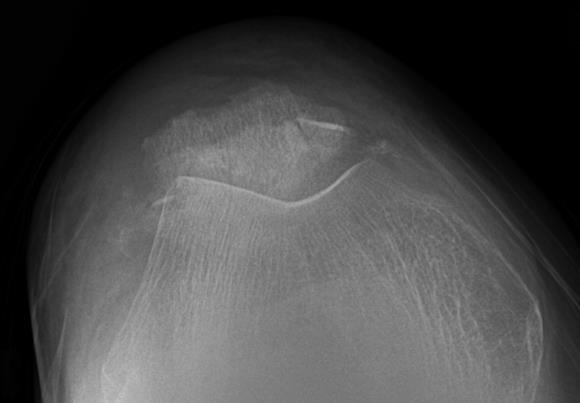

Złamanie rzepki u 82-letniego mężczyzny o konfiguracji jak na przedstawionych obrazach Rtg najkorzystniej jest:

Pytanie 54